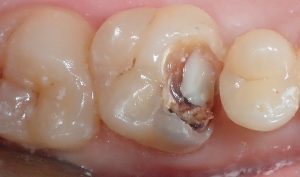

récidive de carie sous une résine ancienne

on voit un gros sequestre!